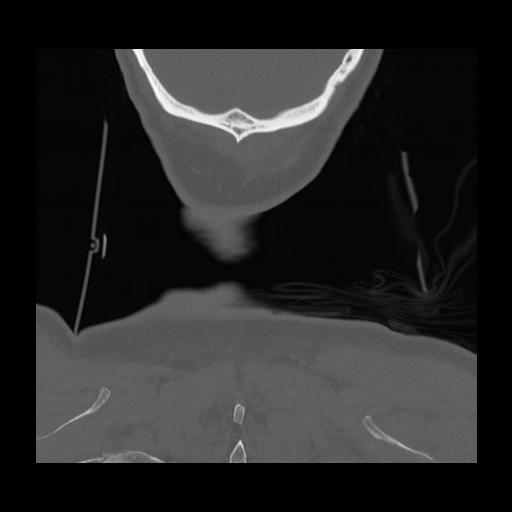

16 HUESO,,Coronal,2.000,HUESO,Coronal,